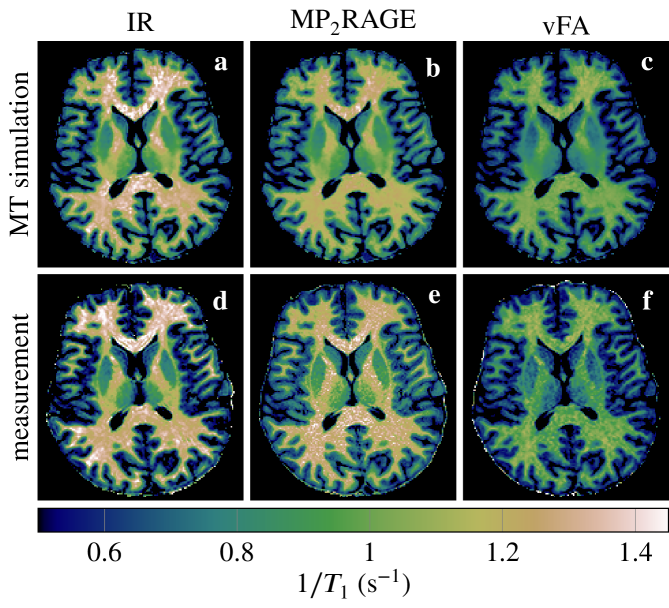

We fitted a mono-exponential model to measured MR data acquired with different pulse sequences. Comparing the resulting maps to one another (Fig.Ā 2) confirms the variability observed in the literature in the absence of biological variability. Performing the same mono-exponential fits on MRI images synthesized with MT simulationsābased on the generalized Bloch model and an unconstrained āresults in maps that closely resemble the measured maps. The biggest deviations are observed for the MP2RAGE sequence.

The median of all white matter voxels in a transversal slice (cf. Fig.Ā 2) is analyzed in Fig.Ā 3. It confirms the agreement between MT simulations and experiments. It also confirms that the MP2RAGE exhibits the biggest deviations. Analyzing the median absolute deviation, we find that MT explains 70% of the variability observed in these experiments.